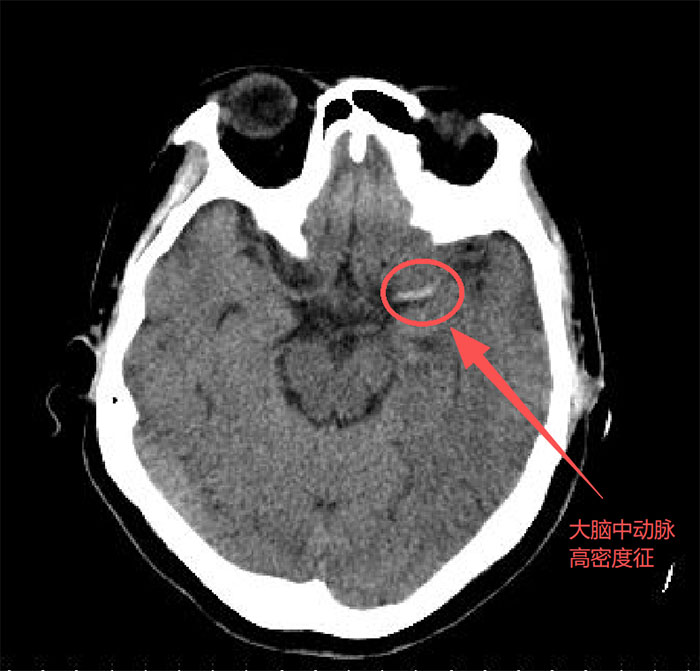

治疗前影像检查

救护车呼啸而至时,我院神经内科卒中团队早已严阵以待。急诊绿色通道迅速开启。经过快速评估和CT检查,徐阿姨被确诊为急性大血管闭塞性脑梗死。这种疾病俗称“脑中风”,每一分钟延误,就有190万个脑细胞死亡。“立即准备溶栓桥接血管内介入取栓!”神经介入医生宫昭城当机立断,立即实施抢救治疗。

在脑血管介入手术室里,一场没有硝烟的战斗打响了。神经介入科主任孟庆贵和科室医生宫昭城,通过患者大腿根部一个针眼大小的穿刺点,将导丝、导管在血管内精准导航,直达脑血管闭塞处。通过造影,可以清晰地看到徐阿姨左侧颈内动脉的主干被血栓完全堵死。